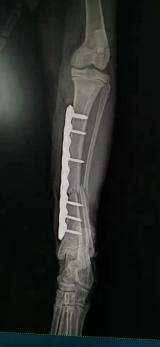

豆皮,小小一只的它被无锡一所高校的学生从垃圾桶里捡出,不知道从何而来,也不知道为何被弃。耳螨、猫癣侵扰着它幼小、羸弱的身躯。雪上加霜的是,豆皮有一天突然被校内疾驰的自行车撞到后腿,骨骼断裂的疼痛让它不得不拖着血肉模糊的伤腿,小心翼翼地向人类乞求一丝生的希望。历时三天,豆皮才被爱心同学送医。

六根钢钉,一块钢板,一个多月的修养复健,万幸的是它在命运的大考中幸存,被当初救助它的同学领养,结束了漂泊无依的前半生。